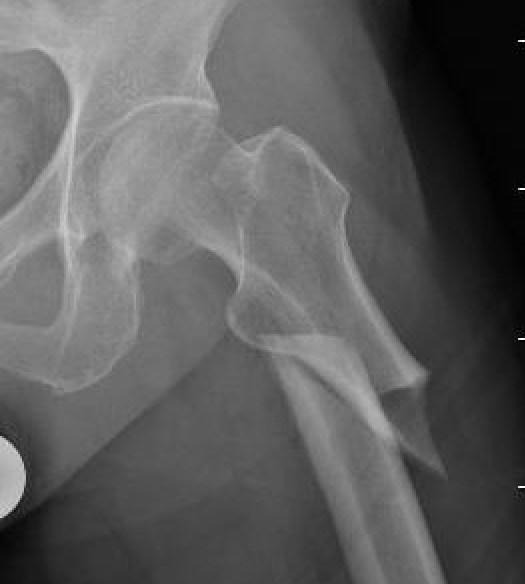

Xray

Periosteal stress reactions / beaking

Thickening of the lateral cortex

- tension side

- most common in the subtrochanteric region

Lateral beaking subtrochanteric region

Lateral beaking femoral shaft

Atypical FFAFF incomplete

Incomplete subtrochanteric AFF